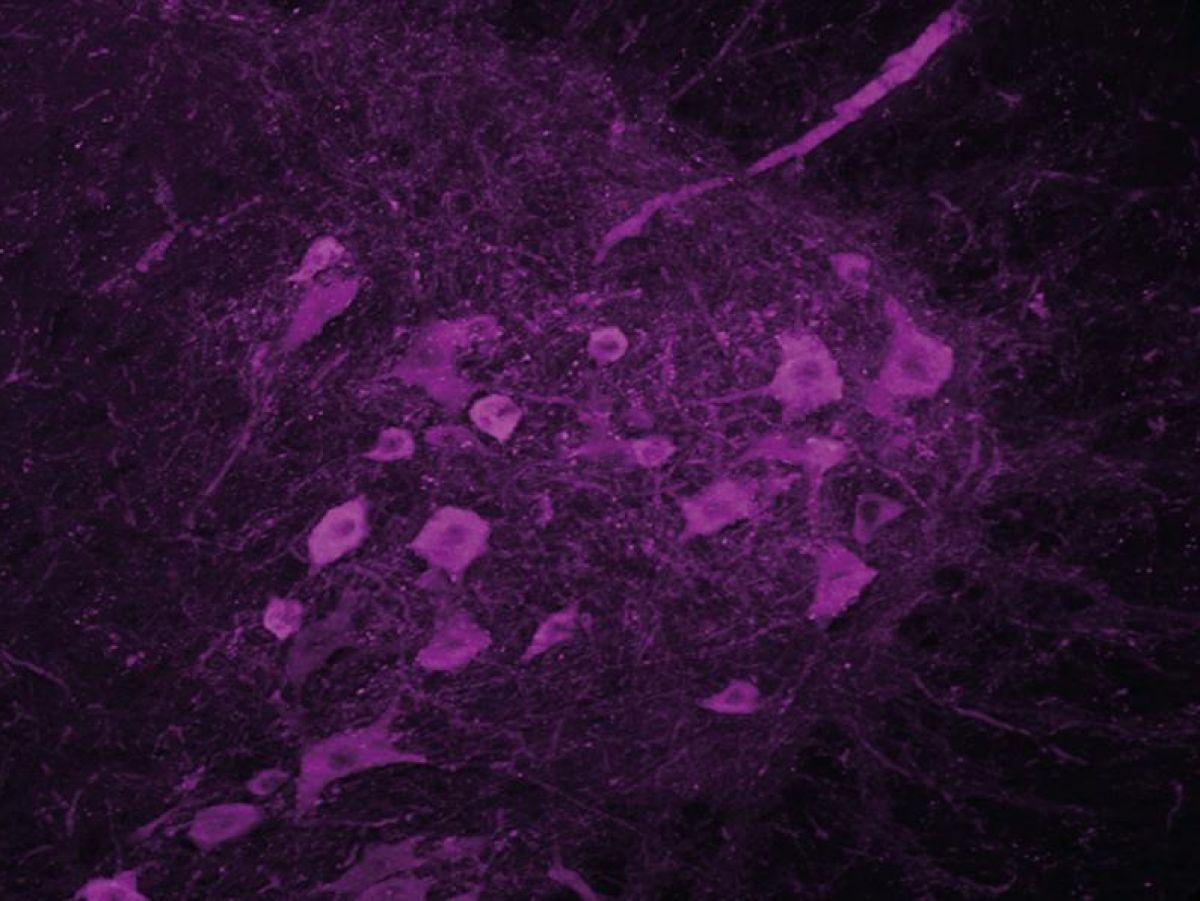

« C’est pour cela que nous nous sommes intéressés à l’hypothalamus, qui est la structure du cerveau en charge de la régulation de notre poids. Nous avons observé que les neurones exprimant l’orexine et la melanin-concentrating hormone (MCH), molécules qui régulent la prise alimentaire mais aussi l’activité et le sommeil, étaient altérés chez les personnes atteintes de SLA, raconte le chercheur. Naturellement, s’il y a des troubles de l’expression de ces neurotransmetteurs dans le cerveau, il y a sûrement aussi des problèmes de sommeil. »

Les souris traitées récupèrent un meilleur sommeil, et leur motoneurone est préservé. »Les motoneurones lombaires semblent ne plus mourir. Ils sont bien là, mais on ne sait pas s’ils sont encore fonctionnels. »